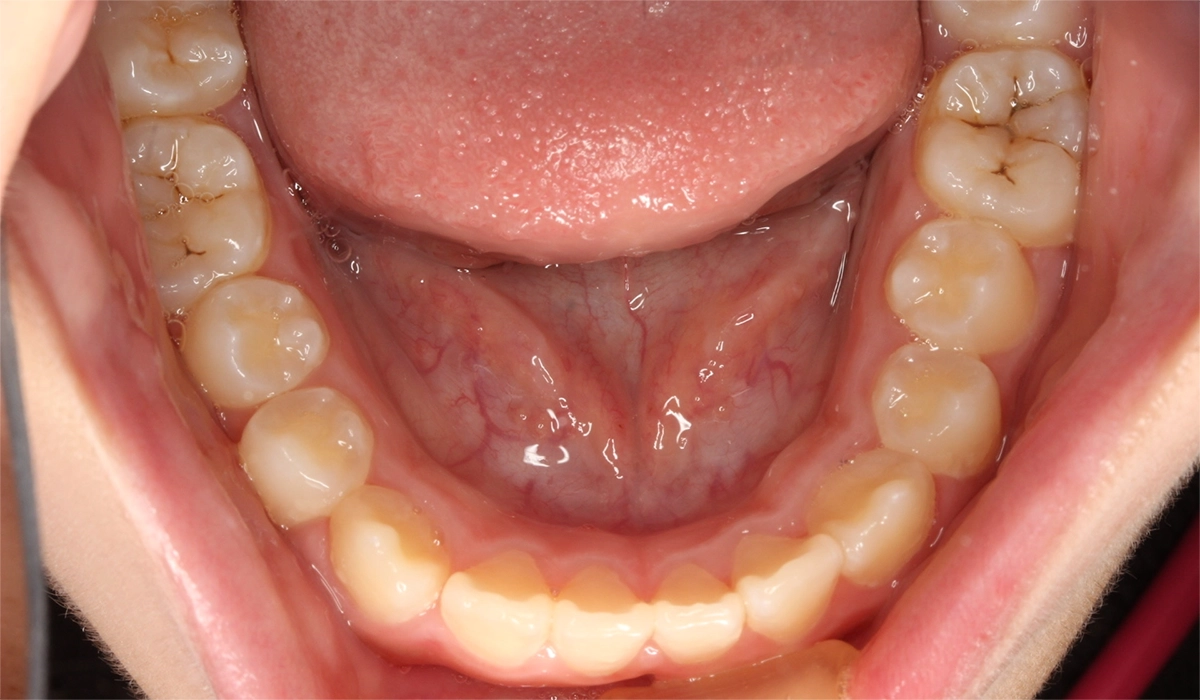

術前:下顎